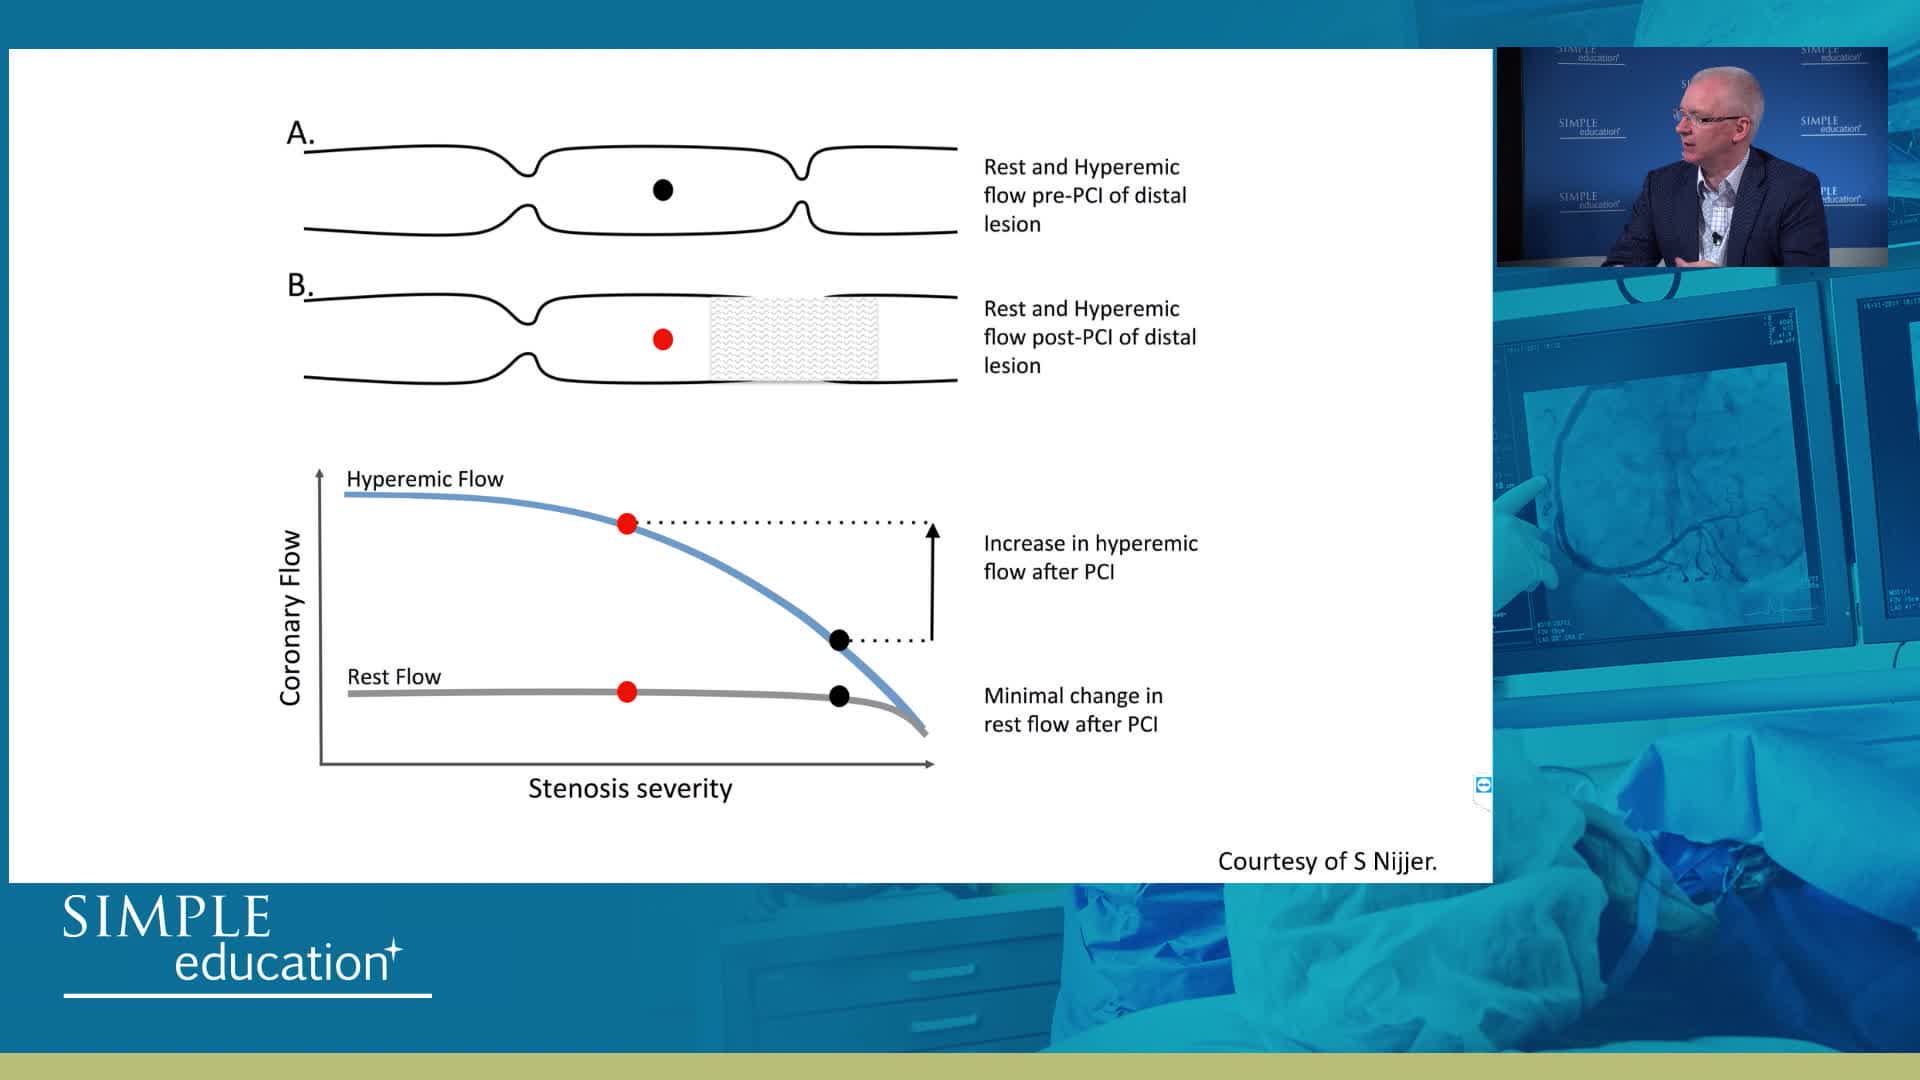

Understanding mechanisms of regulation of resting and hyperaemic blood flow, across single and serial stenoses

Understanding how SyncVision differs from other co-registration based technologies - Dr Justin Davies

Using SyncVision Co-registration to distinguish between focal and diffuse coronary disease. - Prof Giuseppe Tarantini